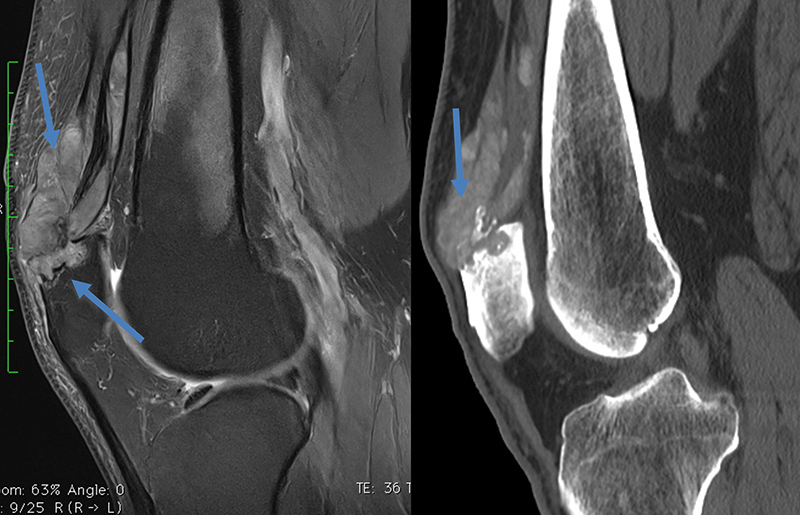

Ostéochodrite disséquante des condyles fémoraux